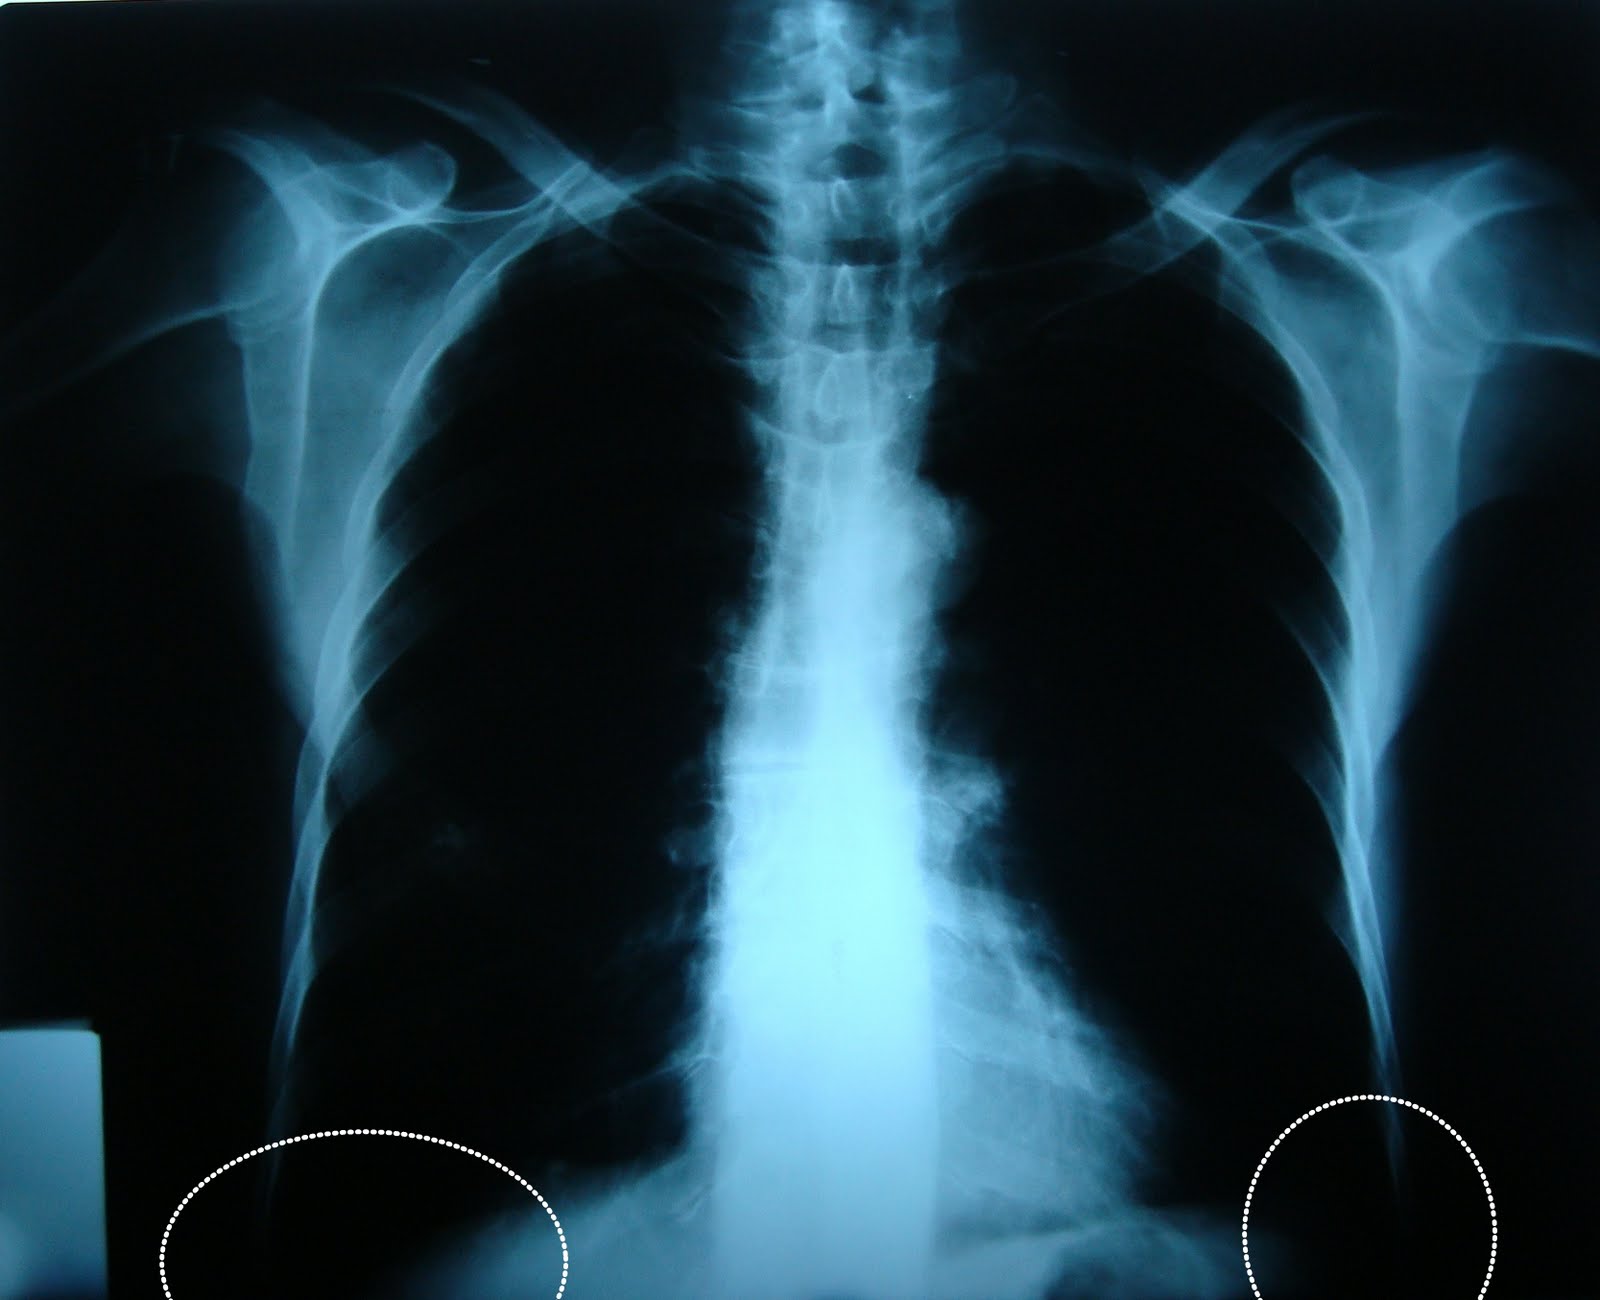

Que Significa Senos Costofrénicos Libres, , , , , , , 0, PPT - RADIOGRAFIA DE TORAX PowerPoint Presentation - ID:6360862, www.slideserve.com, 720 x 540, jpeg, WebSeno costofrénico = costophrenic angle. Es el espacio en la parte externa e inferior de la base de ambos campos pulmonares. Seno costodiafragmático = diaphragmatic angle. Es el espacio en la parte interna e inferior de ambos campos. WebSeno, es un espacio vacio, de ahi que se le diga "seno" a varias partes anatomicas del cuerpo que poseen un espacio. En inglés es angulo, porque es lo. WebSenos costofrénicos libres. No se aprecian imágenes de procesos evolutivos pulmonares focales. Aorta desenrollada. Relación cardiotorácica conservada.. WebLos senos costofrenicos deben estar libres y tener forma afilada. Si estan borrados habra que realizar placas en decubito lateral para ver si existe derrame. Senos costofrenicos., 20, que-significa-senos-costofrenicos-libres, Novedades y Muebles WebSeno costofrénico = costophrenic angle. Es el espacio en la parte externa e inferior de la base de ambos campos pulmonares. Seno costodiafragmático = diaphragmatic angle. Es el espacio en la parte interna e inferior de ambos campos. WebSeno, es un espacio vacio, de ahi que se le diga "seno" a varias partes anatomicas del cuerpo que poseen un espacio. En inglés es angulo, porque es lo. WebSenos costofrénicos libres. No se aprecian imágenes de procesos evolutivos pulmonares focales. Aorta desenrollada. Relación cardiotorácica conservada.. WebLos senos costofrenicos deben estar libres y tener forma afilada. Si estan borrados habra que realizar placas en decubito lateral para ver si existe derrame. Senos costofrenicos.

WebEn cuanto a los senos torácicos se describiría: “Senos costo y cardiofrénicos libres” o “senos costo y cardiodiafragmáticos libres”, entendiendo que son. WebLa palabra Costo se usa para describir enfermedades relacionadas con las costillas y la palabra frénica se usa para describir enfermedades cercanas al. WebMexico/Spanish. Nov 24, 2008. #1. Podria alguien ayudarme con el significado de SCF en el resultado de una radiografia del torax. El texto dice asi: Mala. WebAusência de velamentos ou consolidações no parênquima pulmonar. Diafragma bosselado e seios costofrênicos pouco agudos. Aorta alongada, tortuosa e ateromatosa.. Webcostophrenic / cardiophrenic. Explanation: Se refiere a los ángulos formados entre la caja torácica/costillas (costo) y el diafragma (frénico), y entre el corazón (cardio). WebA continuación, puedes ver ver un listado de opiniones sobre senos costofrenicos libres y opinar sobre este tema. Aquí podrás encontrar opiniones relacionadas con senos. WebAnswers & Comments. Anónimo. Verified answer. Es una parte no visible de tu cuerpo que es necesario ver a la hora de realizar una radiografia pulmonar. Saludos y Paz!

WebThis website uses cookies to improve your experience while you navigate through the website. Out of these cookies, the cookies that are categorized as necessary are stored. WebSe observan ambos senos costofrénicos libres y ausencia de signos de neumotórax. B) Radiografía realizada al tercer día de ingreso. Se observa cómo el ángulo costofrénico. Websenos costofrénicos. Inglés. costophrenic angle. Última actualización: 2012-07-25 Frecuencia de uso: 1 Calidad: Referencia: Wikipedia. Español. sen. Inglés. senna. Última.